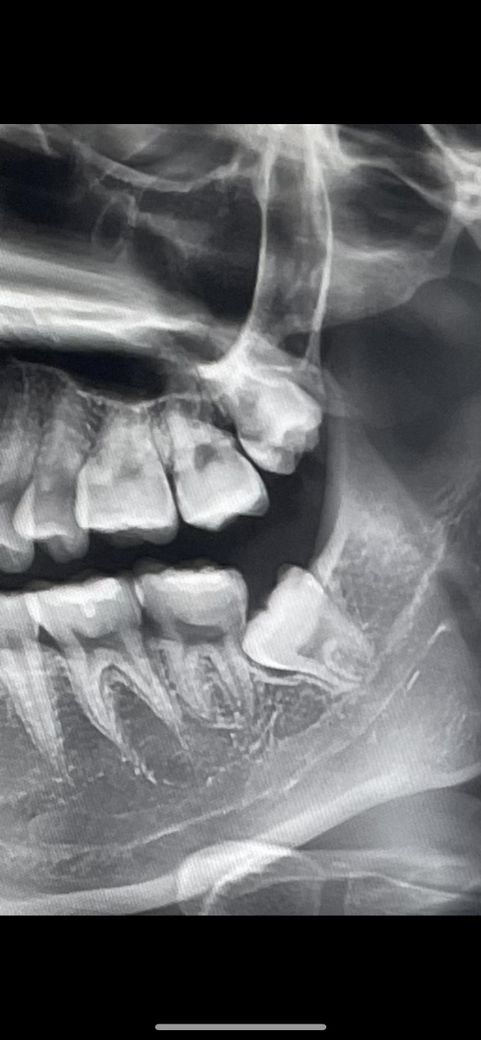

(사랑니 질문) 염증인지 치낭인지 궁금해요 !

왼쪽 아래에 사랑니 질문인데요,

뿌리쪽 말고 머리쪽 아래에 뭔가가 있는데

치낭인지 염증인지 궁금해요 !

다른 치아와 맞닿은 부위가 썩을 가능성이 있어 보이는지, 이 사랑니를 뽑으면 좋을지도 궁금합니다~

치아가 치조골 안에 있을때는 머리부분이 막에 쌓여 있습니다.

그부위가 어둡게 보이는 부분이에요.

크게 문제가 되지는 않지만 사랑니가 잇몸밖으로 나오게 되어 이물질이 끼어 있게 되면 충치가 생길수 있기 때문에 발치를 하는것이 좋습니다.

사랑니 머리 부분에 아무것도 잇는 상태가 아닙니다. 그냥 잇몸이 덮혀 있는거 같습니다. 사랑니앞치아가 썩엇을 가능성이 있어 보입니다.

염증은 아니고 치아가 맹출 시 반응해서 생긴 구조입니다 현재 사랑니가 그 앞 어금니를 밀고 있으므로 치근흡수, 충치의 가능성이 있습니다 부분매복의 경우 예방적 발치가 권장되기도 합니다